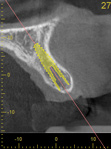

Fig 2. CBCT images show axial (Fig 2) and cross-sectional (Fig 3) views, and 3D reconstruction view (Fig 4) with virtually planned implant Nos. 8 and 9.

Figure 2

Fig 3. CBCT images show axial (Fig 2) and cross-sectional (Fig 3) views, and 3D reconstruction view (Fig 4) with virtually planned implant Nos. 8 and 9.

Figure 3

For dental implant-based treatment, the planning phase begins with collection of basic data sets; this is digital touchpoint 1. It includes: (1) a cone-beam CT (CBCT) to view edentulous areas or failing tooth structure, bone, and anatomic landmarks under the soft tissue (Figure 2 through Figure 4); and (2) an intraoral optical scan (IOS) or a scanned model or impression to record the soft tissue and tooth anatomy (Figure 5). The superimposition of the digital imaging and communications in medicine (DICOM) files from the CBCT and the standard tessellation language (STL) files from the IOS allows visualization of how bone, dental structures, and soft tissues relate. Both digital data points are key to implant selection and determining the surrounding bone-grafting needs. An initial treatment plan includes determining the desired implant manufacturer/implant design, size, and positions; these decisions remain the responsibility of the dentist (restoring and surgical team members) and not the technician or planning team.